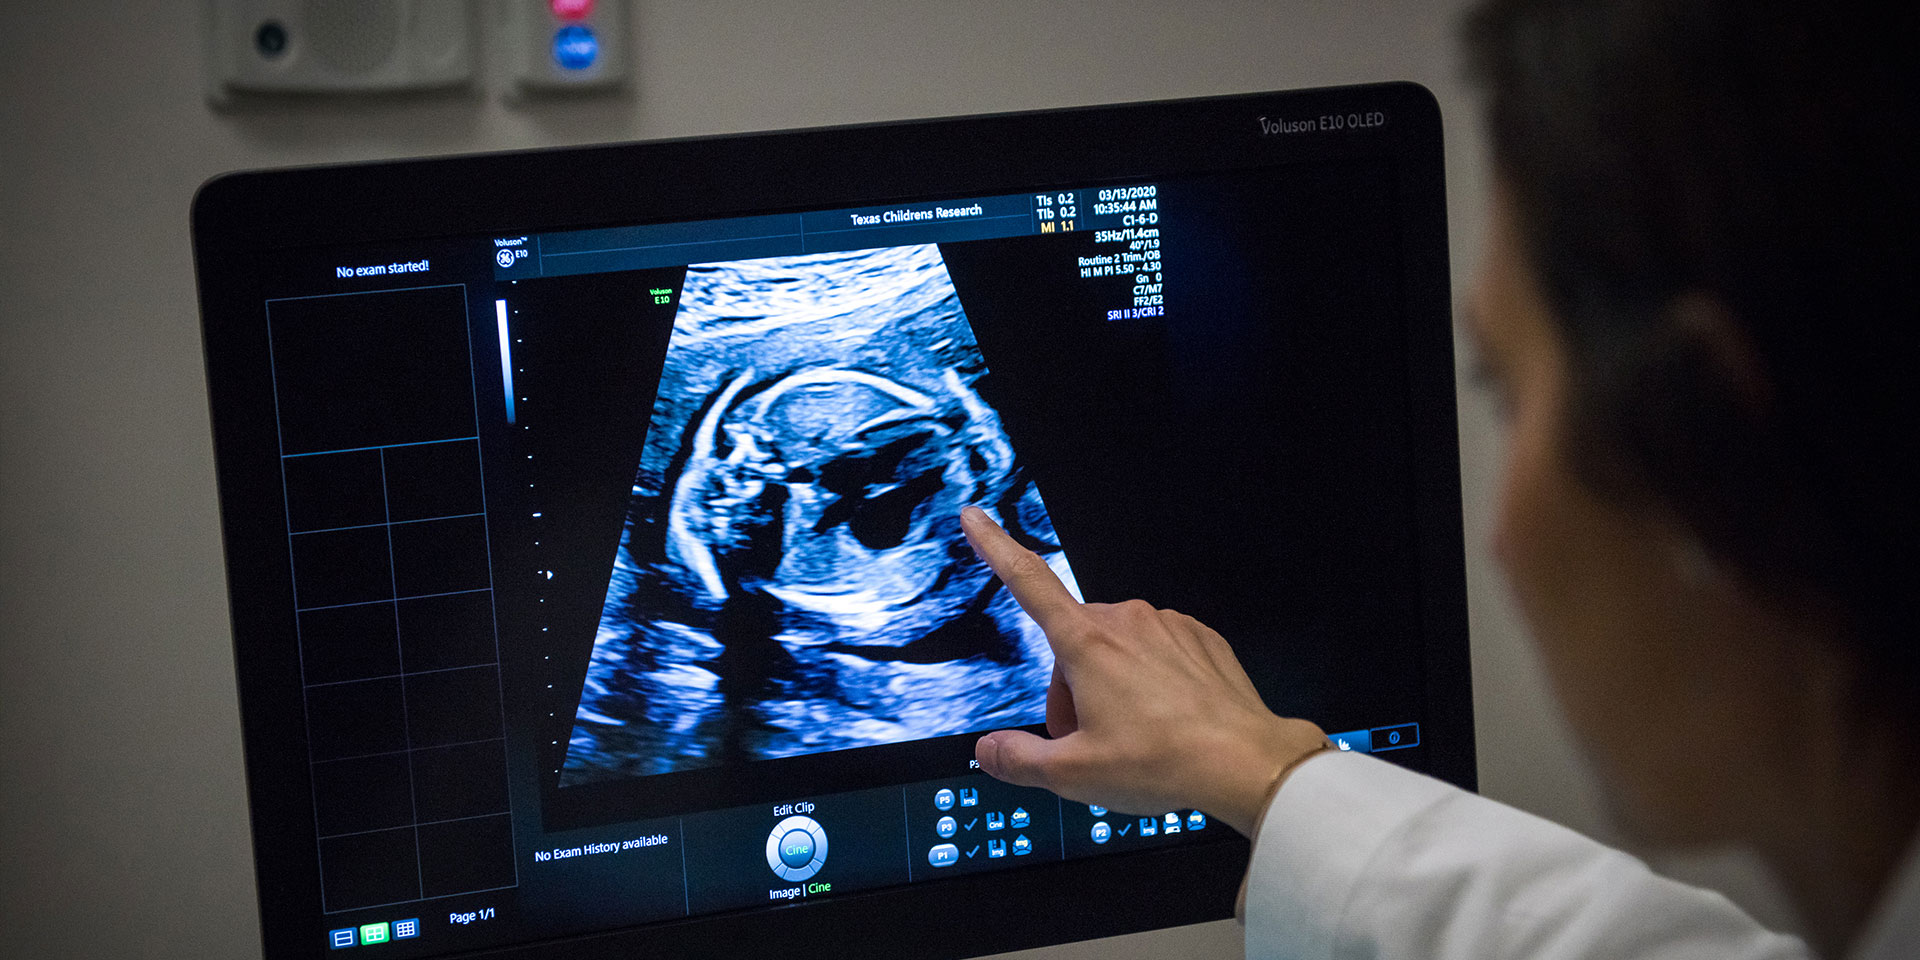

For more than 30 years, Texas Children’s Fetal Cardiology program has provided comprehensive fetal cardiac care to expecting families when there is a concern for or risk of heart disease in the fetus. In partnership with Texas Children’s Fetal Center, this care includes diagnosis, counseling, delivery planning and then transition to treatment at Texas Children’s Heart Center after birth. Our collaborative model allows patients to receive the best care from a team of specialists, all in one location.

We have immense expertise and experience in fetal cardiology given our long history and high volume. We currently have 16 fetal cardiology providers highly trained in fetal cardiac imaging. Our vast experience following fetuses through gestation, delivery, infancy and adulthood gives us unique insight and ability to make accurate diagnoses and formulate the best care plans.

For fetuses with some cardiovascular conditions, fetal cardiac intervention is available at Texas Children’s Hospital to try to improve the physiology of the heart before birth. Texas Children’s Fetal Center is one of only a few centers in the world capable of providing the full array of fetal cardiac interventions, which involves a coordinated effort among a large, multidisciplinary team of fetal cardiologists, interventional pediatric cardiologists, congenital heart surgeons, maternal fetal medicine experts, maternal and fetal anesthesiologists, and other clinical specialists.